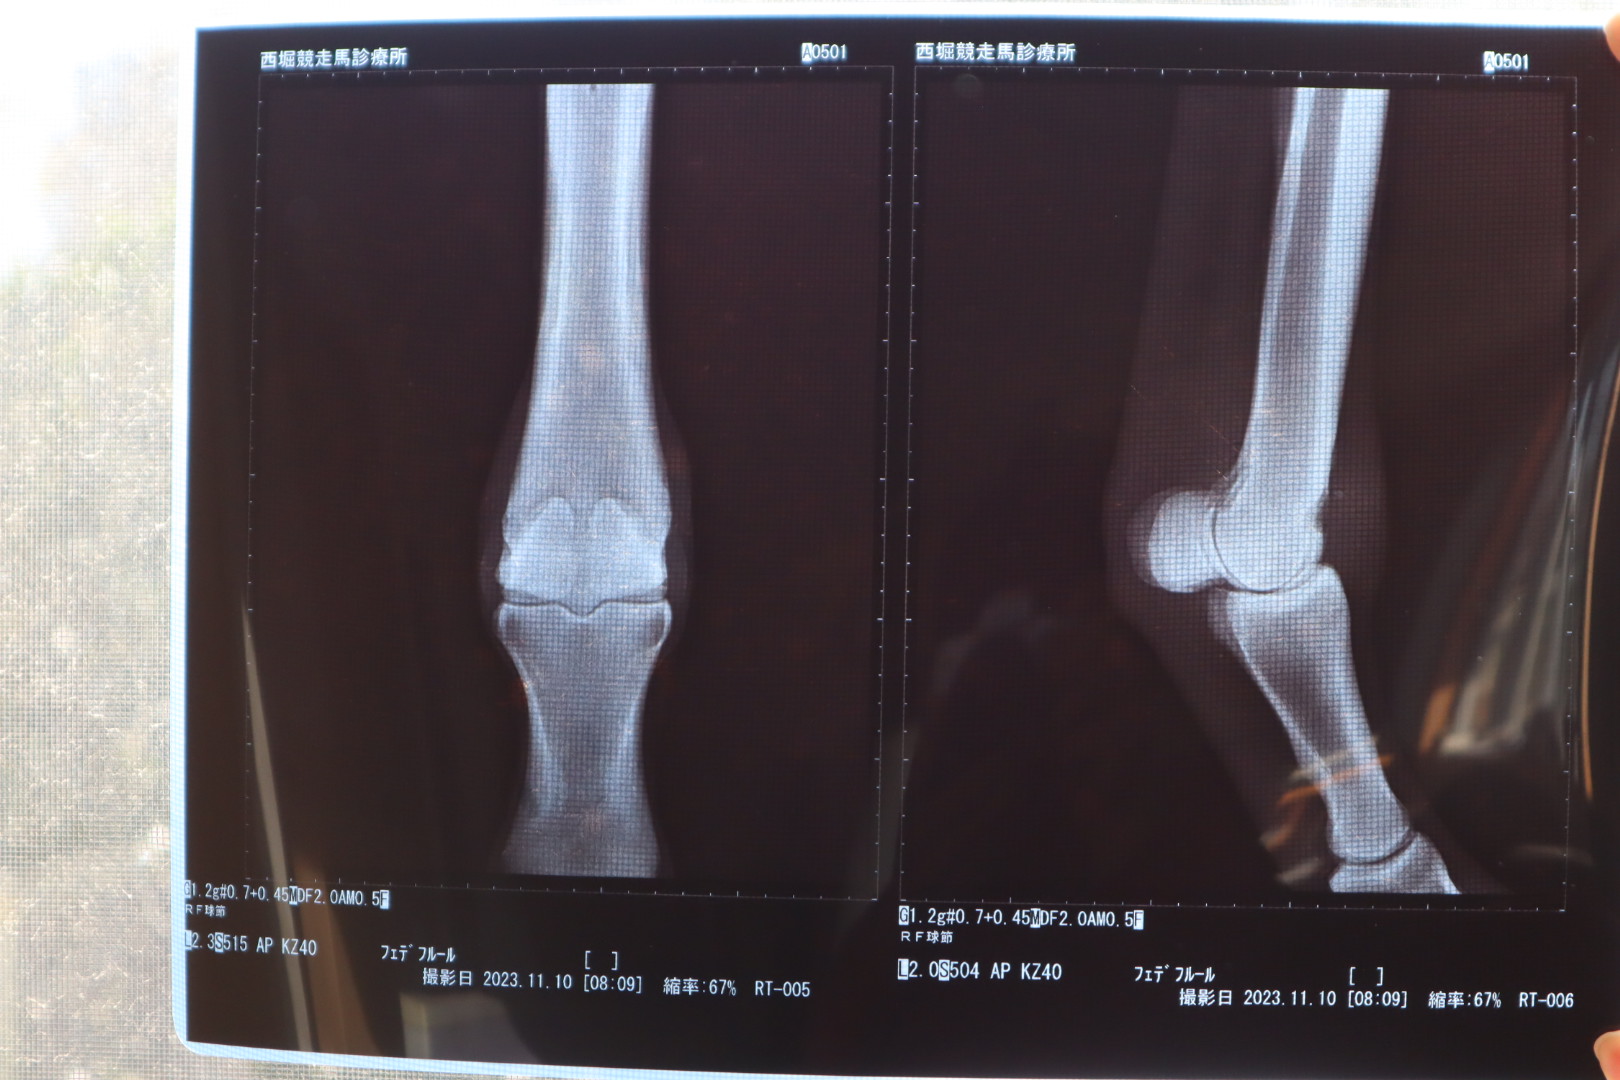

なお、オークション出品に伴い、2023年11月10日にレントゲン撮影を行ったところ、右前球節前面部に僅かに骨膜が確認されています。